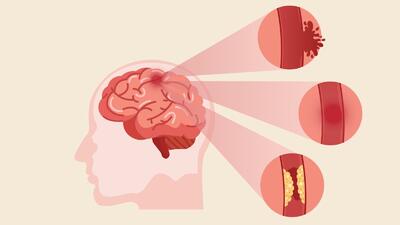

رگها را پس از سکته ترمیم می شوند

این ساختار سه بعدی مولکولهای درمانی را پس از سکته به مغز میرساند.